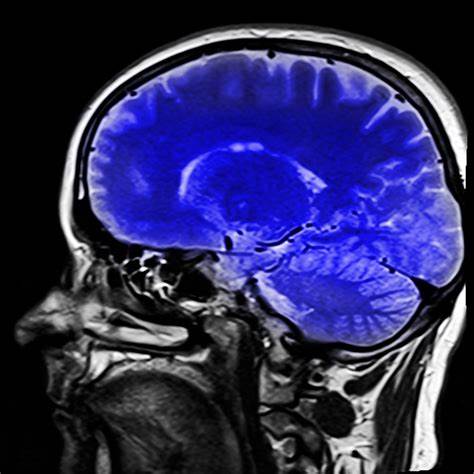

1. 뇌종양 (예: 교모세포종)

- 형광물질: 5‑ALA → PpIX(프로토포르피린 IX) 형성

- 특징: 수술 전 5‑ALA 경구 투여 → 종양 조직이 붉게 형광 발광

- 임상 활용: 유럽·일본·한국 일부 병원에서도 뇌수술 중 사용 중

- 장점: 종양과 정상 뇌 조직 경계가 뚜렷해 수술 정확도 증가